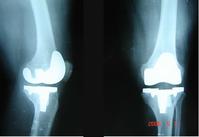

关节炎图片